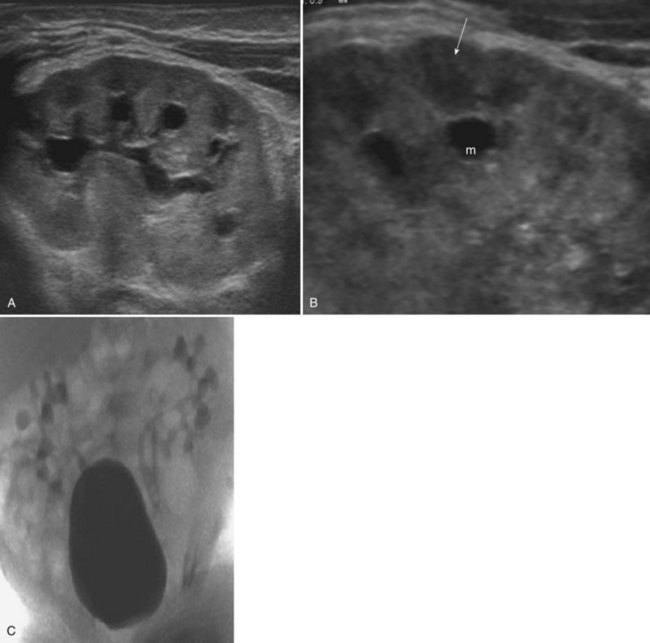

Figure 117–21 Megacalycosis. A, Sagittal ultrasonogram shows dilated calyces and normal-appearing pyramids. B, Enlarged view of A demonstrates distinct megacalyx (m) and normal pyramid (arrow). C, Voiding cystourethrogram shows bilateral vesicoureteral reflux into megacalyces.

Megacalycosis is congenital and has been diagnosed prenatally (Vidal Company et al, 2001). It occurs predominantly in males with a ratio of 6 : 1 and has been found only in whites. Bilateral disease has been seen almost exclusively in males, whereas segmental unilateral involvement occurs only in females (Cacciaguerra et al, 1996), suggesting an X-linked partially recessive gene with reduced penetrance in females (Gittes, 1984). Except for one report of two affected brothers, the entity has not been thought to be familial (Briner and Thiel, 1988).